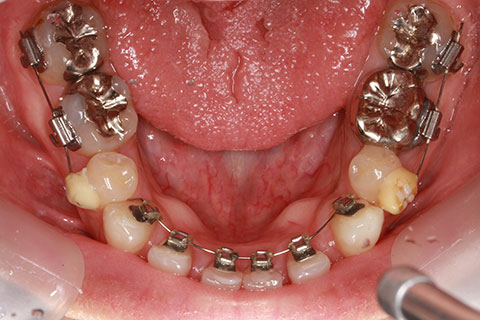

矯正期間18ヶ月

フルリンガル矯正2(上下の歯を舌側矯正で治療)

治療前

治療中

治療後

- 年齢・性別

- 42歳男性

- 治療期間

- 1年6ヶ月

- 抜歯

- なし

- 治療費

- 120万円(税込み)

- 備考

- マルチブラケットを用いた矯正治療

- 治療内容

- 反対咬合をフルリンガル矯正治療にて改善

- 施術の副作用(リスク)

- 表側矯正と比較して、歯根の角度を確立する「トルク」の力がかかりにくい。